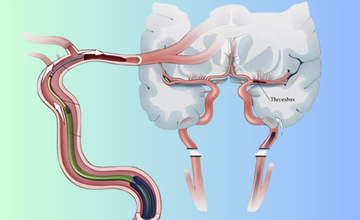

A minimally invasive endovascular procedure removing clots from blocked brain arteries, restoring blood flow, and reducing disability after stroke.

Restores blood flow by removing clots, improving outcomes and reducing disability in acute stroke patients.